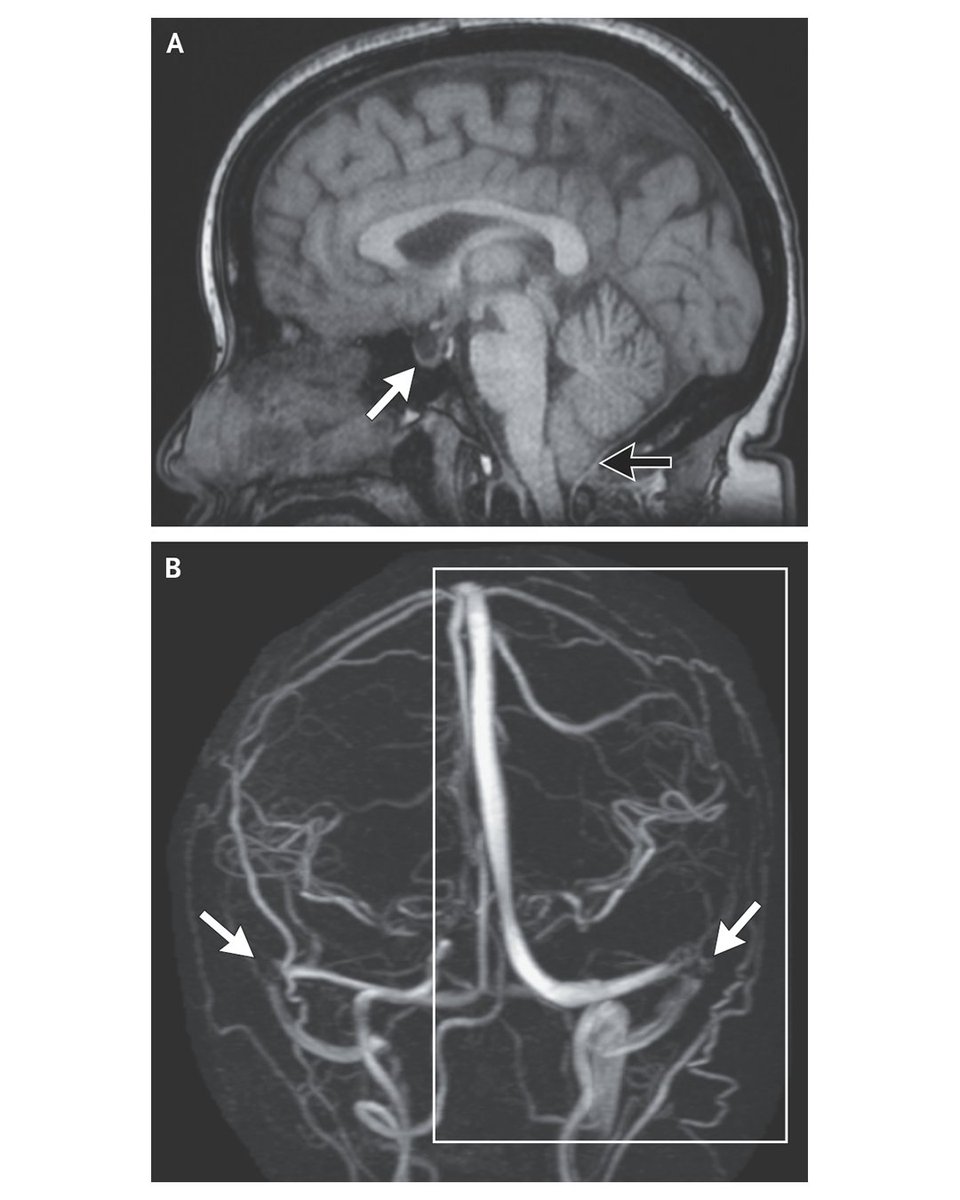

Persistent Trigeminal Artery (<1% prevalence) – A rare embryonic remnant that connects the ICA with the basilar artery It may serve as a collateral pathway but can be associated with a variety of vascular lesions

Persistent Trigeminal Artery (&lt;1% prevalence) – A rare embryonic remnant that connects the ICA with the basilar artery

It may serve as a collateral pathway but can be associated with a variety of vascular lesions